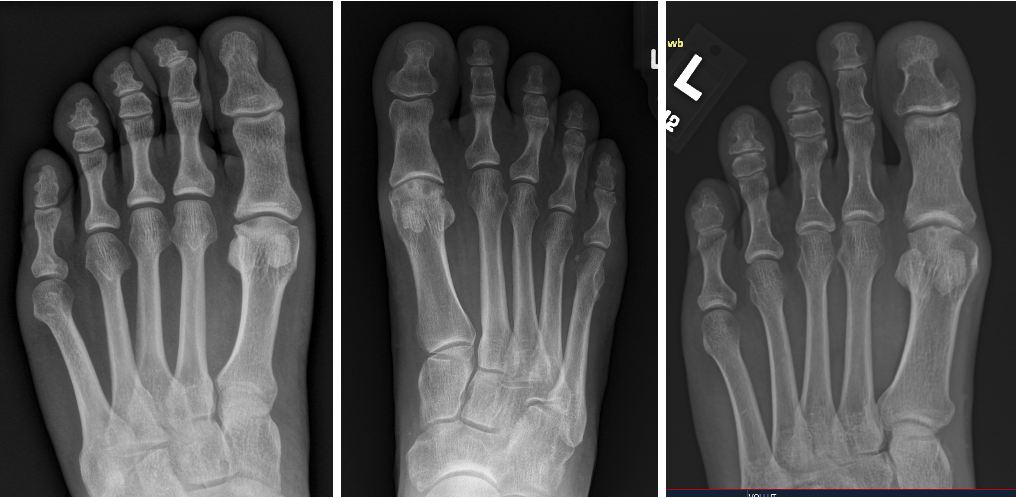

Once we can establish first MTPJ symptoms, then we have to start looking at the various structures. Find out if you are dealing with sesamoiditis, sesamoid alignment issues, synovitis, chondromalacia, loose bodies, osteophytes, avascular necrosis of the sesamoids, or arthritis of the crista, as shown in Ross’s Podiatry Today article in April 2015.4 This is where magnetic resonance imaging (MRI) comes in and is very helpful, just as we discussed in my articles on first MTPJ arthroscopy in August 2019 and turf toe injuries in May 2011.5,6

There have been several review papers that looked at staging and various classifica-tion systems, and none ever takes into account chondromalacia. I have shown many cases over the years where systems would classify patients as Stage I, but in reality, they had significant full-thickness defects of the metatarsal head, as shown in Figure 1. Despite little to no osteophytes, many athletes will have adequate dorsiflexion without pain. Pain only existed with activity and weightbearing. None of the classification systems takes into account sesamoid position, which is crucial for predicting potential crista damage.